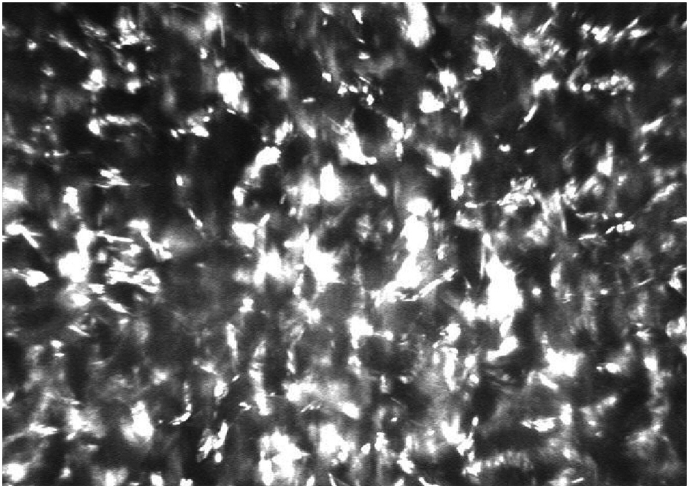

Fig. 2.

In vivo confocal microscopy of the RE, showing numerous highly reflective deposits in the corneal stroma.

The visual acuity of his right eye (RE) was 0.6 (6/10 Snellen) and of his left eye (LE) 0.8 (6/7.5 Snellen) without correction. The visual acuity did not improve with glasses. Slit-lamp examination revealed fine iridescent confluent corneal crystals in both eyes, distributed throughout all corneal layers, both peripherally and centrally (Fig. 1A, Fig. 1B). Mild anterior uveitis was observed in the right eye (Tyndall 1+; cells 1+). His lenses were clear and no abnormal ophthalmoscopic findings were observed. The intraocular pressures were normal, at 11 mm Hg in the RE and 10 mm Hg in the LE. Optical coherence tomography (OCT) revealed fine, hyper-reflective dot-shaped deposits across all layers of the cornea in both eyes (Fig. 1C). In vivo confocal microscopy (IVCM) showed highly reflective deposits throughout the cornea in both eyes (Fig. 2).